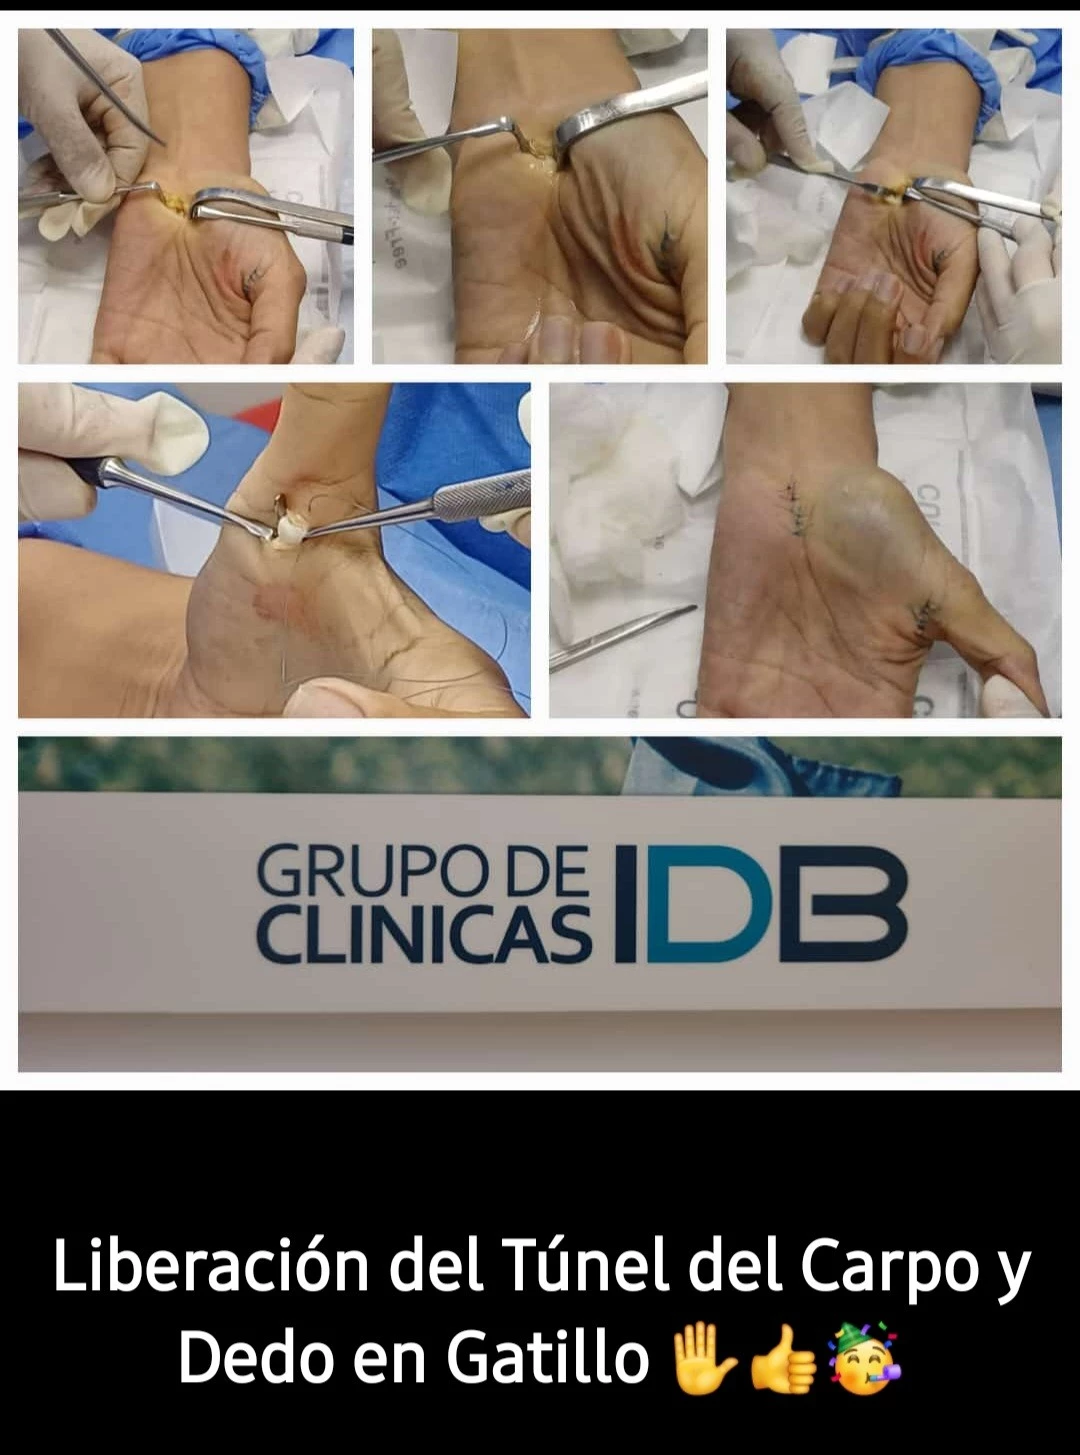

LIBERACION DEL TUNEL DEL CARPO Y DEDO EN GATILLO

PACIENTE FEMENINA QUE ACUDE PARA LIBERACION DE DEDO EN GATILLO Y TUNEL CARPIANO